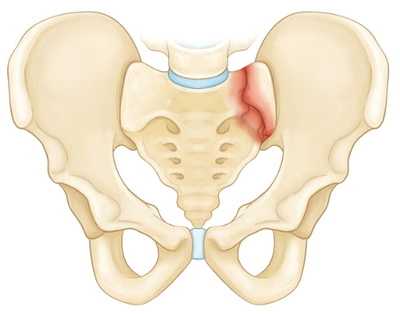

Нестабильные переломы. Данный тип переломов характеризуется нарушением целостности тазового кольца как минимум в двух точках, при котором анатомия таза, как правило, нарушается (происходит смещение фрагментов). Чаще всего такие переломы возникают вследствие высокоэнергетической травмы. К нестабильным переломам относят следующие:

Повреждение в результате передне-задней компрессии таза.

- Стабильные (переломы костей таза, не сопровождающиеся нарушением целостности тазового кольца). В эту группу входят изолированные и краевые переломы костей таза.

- Нестабильные (переломы костей таза, сопровождающиеся нарушением целостности тазового кольца). В зависимости от механизма травмы возможно возникновение вертикально нестабильных и вращательно нестабильных переломов. При вертикально нестабильных переломах костей таза целостность тазового кольца, как правило, нарушается в двух местах: в заднем и переднем отделе. Отломки смещаются в вертикальной плоскости. При вращательно (ротационно) нестабильных переломах со смещением смещение отломков происходит в горизонтальной плоскости.

- Переломовывихи костей таза. При этом виде повреждений перелом костей таза сочетается с вывихом в лонном или крестцово-подвздошном сочленении.